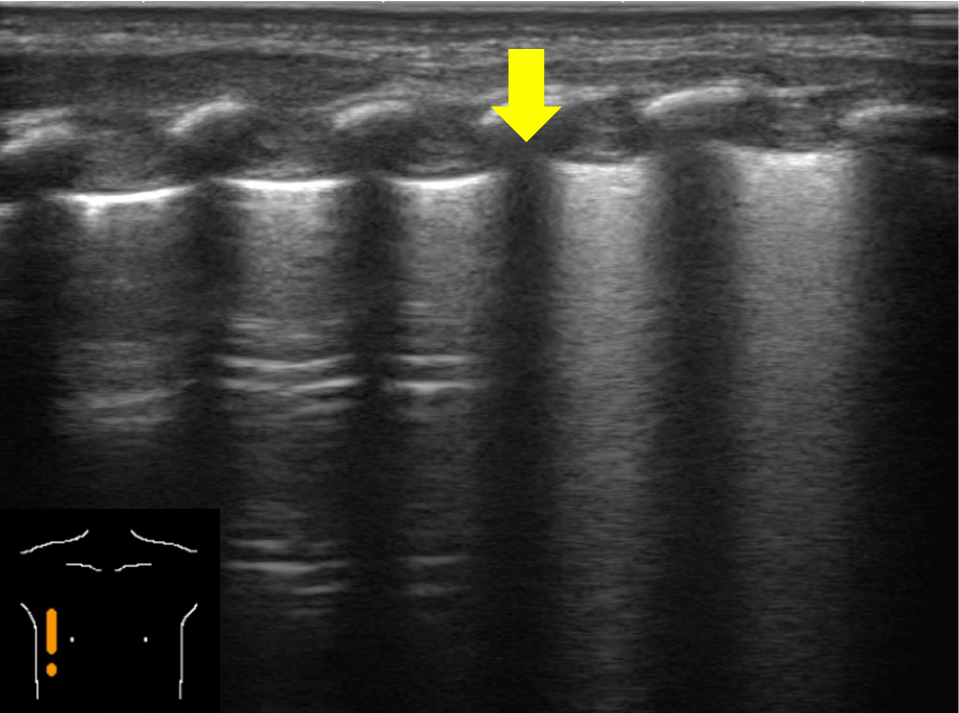

5)Seashore sign, stratosphere sign/barcode sign(Mモード)Mモードを用いて,肺の動きを表した所見である.胸膜ラインより浅部の軟部組織は動きがほとんどないため,線状の画像を呈し,海の波(sea)のように見える.胸膜ラインより深部は呼吸により動くため,ノイズによって砂浜(shore)のように見える.胸膜ラインを境目に海と砂浜のように描かれるためseashore signと呼ばれる(Fig.7).一方で気胸があると,胸膜直下の空気に動きがないため胸膜ラインでの境目がなくなり,薄い層が連なっているように見える.これを空気が層状に重なる成層圏(stratosphere)に例えて,stratosphere sign/barcode signと呼ぶ.

カーソルは胸膜に合わせる.胸膜ライン(黄色矢頭)より浅部は線状を呈し,胸膜ライン(黄色矢頭)より深部はノイズとなる.胸膜ラインを境目に海と砂浜のように描かれる.

気胸を診断するための超音波検査では,仰臥位の患者の第2–3肋間鎖骨中線にプローブを置き,bat signを描出する.Lung slidingの消失(Movie 3),B lineの消失,lung pulseの消失,またはlung pointの存在(Movie 4)を総合してプローブを当てた領域の気胸を診断する(各用語はTable 1を参照).また,診断の補助としてMモード画像所見(Fig.10)も気胸診断の根拠となるため,特に小児では積極的に使用して良いだろう.

胸膜上は呼吸性変動が極めて少ないため直線状となる.一方,胸膜下は,正常肺では呼吸性変動により頼粒状に,気胸では呼吸性変動がないため直線状となる.前者は海岸の砂浜になぞらえてseashore sign,後者はstratosphere signまたはbarcode signと呼ばれる.